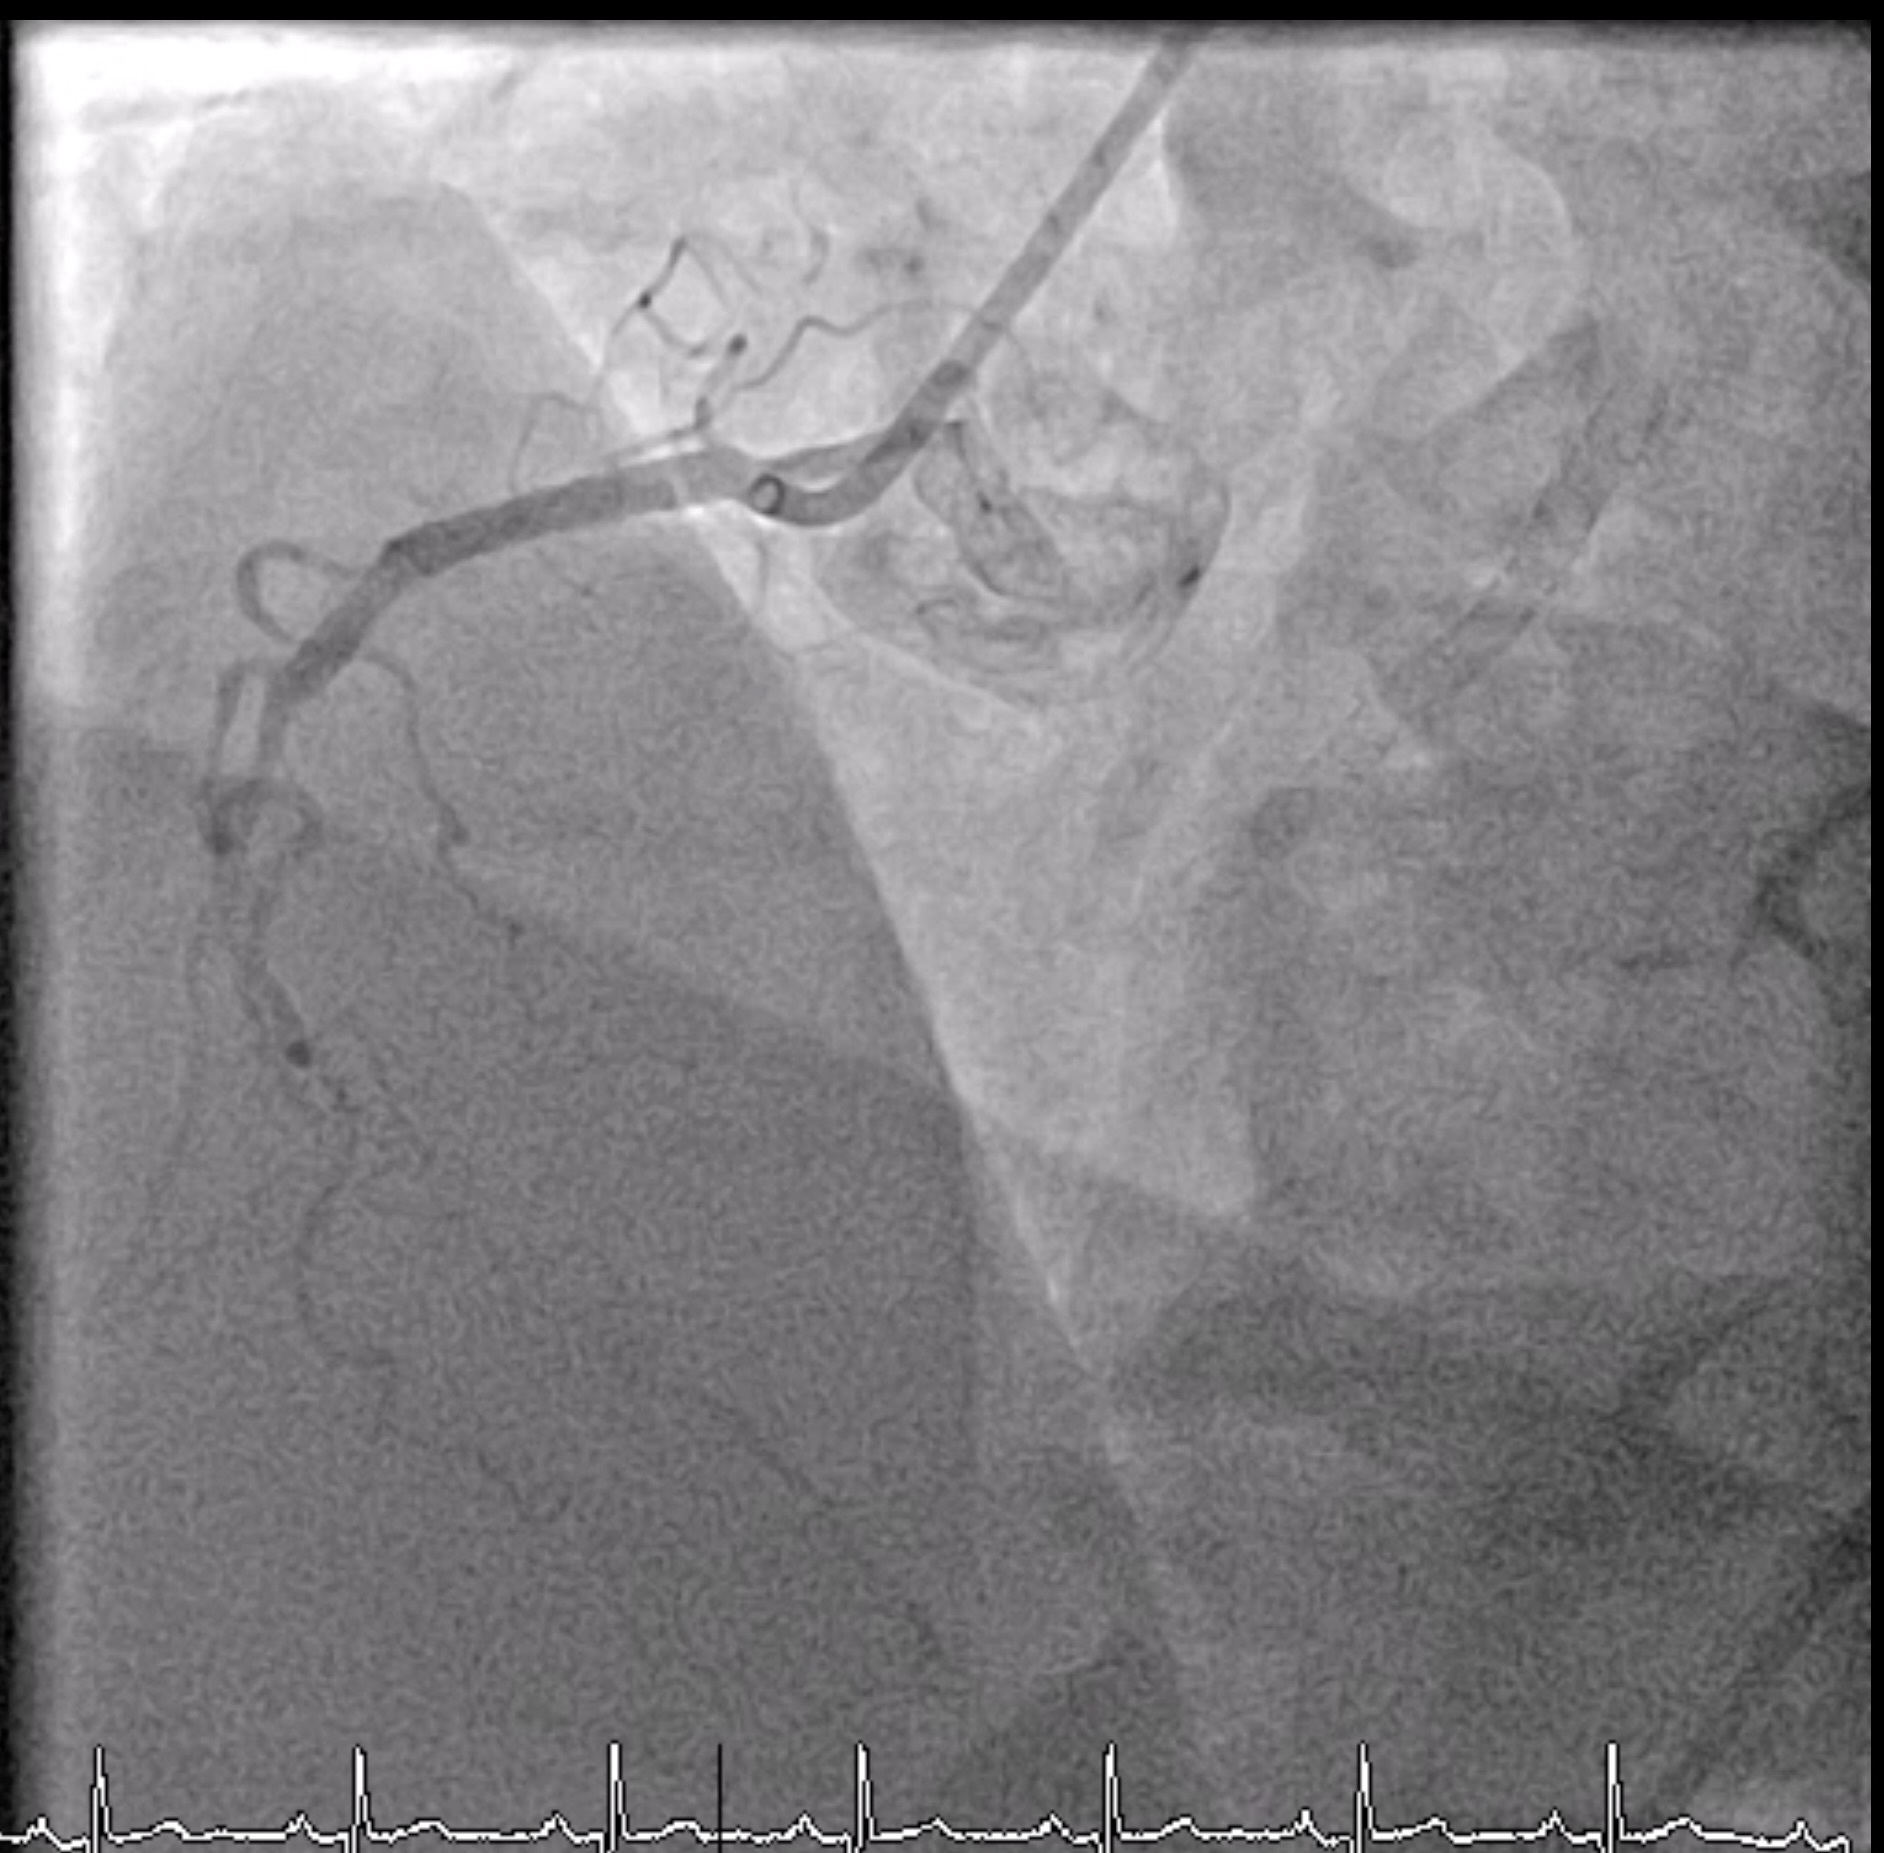

Microcatheter (Finecross) with Fielder XT to RCA, unable to pass the CTO lesion then changed to Gaia 2nd which was unsuccessful too and finally changed to Gaia 3rd. Gaia 3 rd guidewire got stuck at distal RCA. Snare catheter 8 mm was inserted to retrieve Gaia 3rd guidewire which was unsuccessful (Several attempts). Turntrac guidewire and Fielder-XT was inserted across the lesion to twist wire for Gaia 3rd retrieval, but failed and complete fracture of all three wires happened. Snare Size 8 mm was inserted for retrieval but failed.Smaller snare size 7 mm and 4 mm were inserted for retrieval but failed.Left femoral artery puncture with 8 Fr. Sheath. Guiding catheter JR 4.0/7 was used. Snare 8 mm and 15 mm via LFA could retrieve some part of wire. Decided to leave the wire at RCA due to several failed attempts. Angiogram was done before stopping the procedure. As we were removing the catheter, thin stretched guidewires were seen floating in the ascending aorta till descending aorta. Snare 15 mm could remove the wire floating in the aorta after several attempts.Final angiogram showed retained some parts of fractured guidewires and planned to leave it there. The patient was asymptomatic and hemodynamically stable.